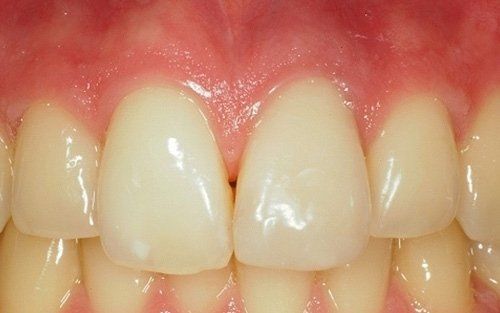

Frequenti, in età pediatrica, sono i traumi (sportivi e non). Come conseguenza i denti anteriori superiori (ovvero gli incisivi) sono i più esposti all’evento che può esitare in una frattura della corona con o senza il coinvolgimento della polpa, nella necrosi del dente (che può avvenire, più facilmente, senza alcuna frattura della corona dentale), oppure in quel panel di complicanze che vanno dalla lussazione ai traumi intrusivi o estrusivi, fino all’ avulsione, cioè la fuoriuscita completa del dente dall’alveolo.